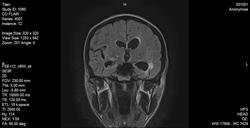

Направлен с диагнозом энцефаломиелит? минингит ? абсцесс мозга? Пациенту 26 лет, тугоухость, судорожный синдром.

Я дмаю о менингоэнцефалите, возможно ВИЧ+Туберкулез.

Асимметричная внутренняя гидроцефалия с лейкоареозом(?) у передних и задних рогов-почему-то только слева ; шишковидная железа выглядит увеличенной , а очаги - все инфратенториальные . Не понятно, 8 картинка - это диффуз ? Для 26 лет -много всего . Анамнез и клиника должны быть интересней , чем Вы пишите ( там- больше половины диагноза ) . Как давно болен ? Температура какая ? Не наркоман ? Если думать об постинфекционном энцефаломиелите , то что было 2 нед назад ? (Прививка , химиотерапия , острая инфекция )

Насколько я понял, был 2х сторонний отит около месяца или 2х назад. Но последние недели температуры нет. Наркоман или нет - не ясно. Что за очаг между пластинкой четверохолмия и мозжечком? И не давит ли оно на водопровод. Да и мысли ещё о токсоплазме.

В 26 рановато совсем , но- на простое обызвествление шишковидной похоже . А тугоухость -сразу через месяц после хорошего острого( может- гнойного ?) отита -это интересно . Хороший вариант -после отита еще не восстановились повреждения барабанной перепонки . Очаги при постинфекционном энцефаломиелите- обычно субкортикальные . А тут - локализация вроде не совпадает . НО! Это может быть осложнением острого среднего отита- -внутричерепные абсцессы . Они ( очаги) и анатомически близко расположены к внутреннему слуховому проходу . Что и подтверждает важность АНАМНЕЗА !

А почему это не может быть демиелинизирующим процессом?